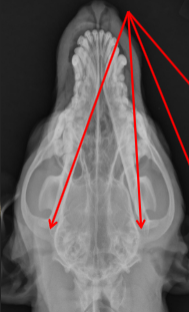

ID radiographic view

VD

Open Mouth VD view of Nasal Cavity

ID

Ethmoid Turbinates

Maxillary Turbinates

VOmer Bone

Palantine Foramen

Frontal Sinus View